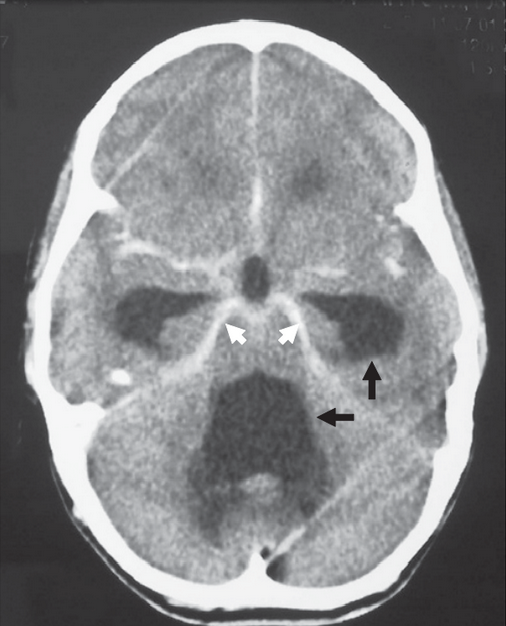

Méningite tuberculeuse.png